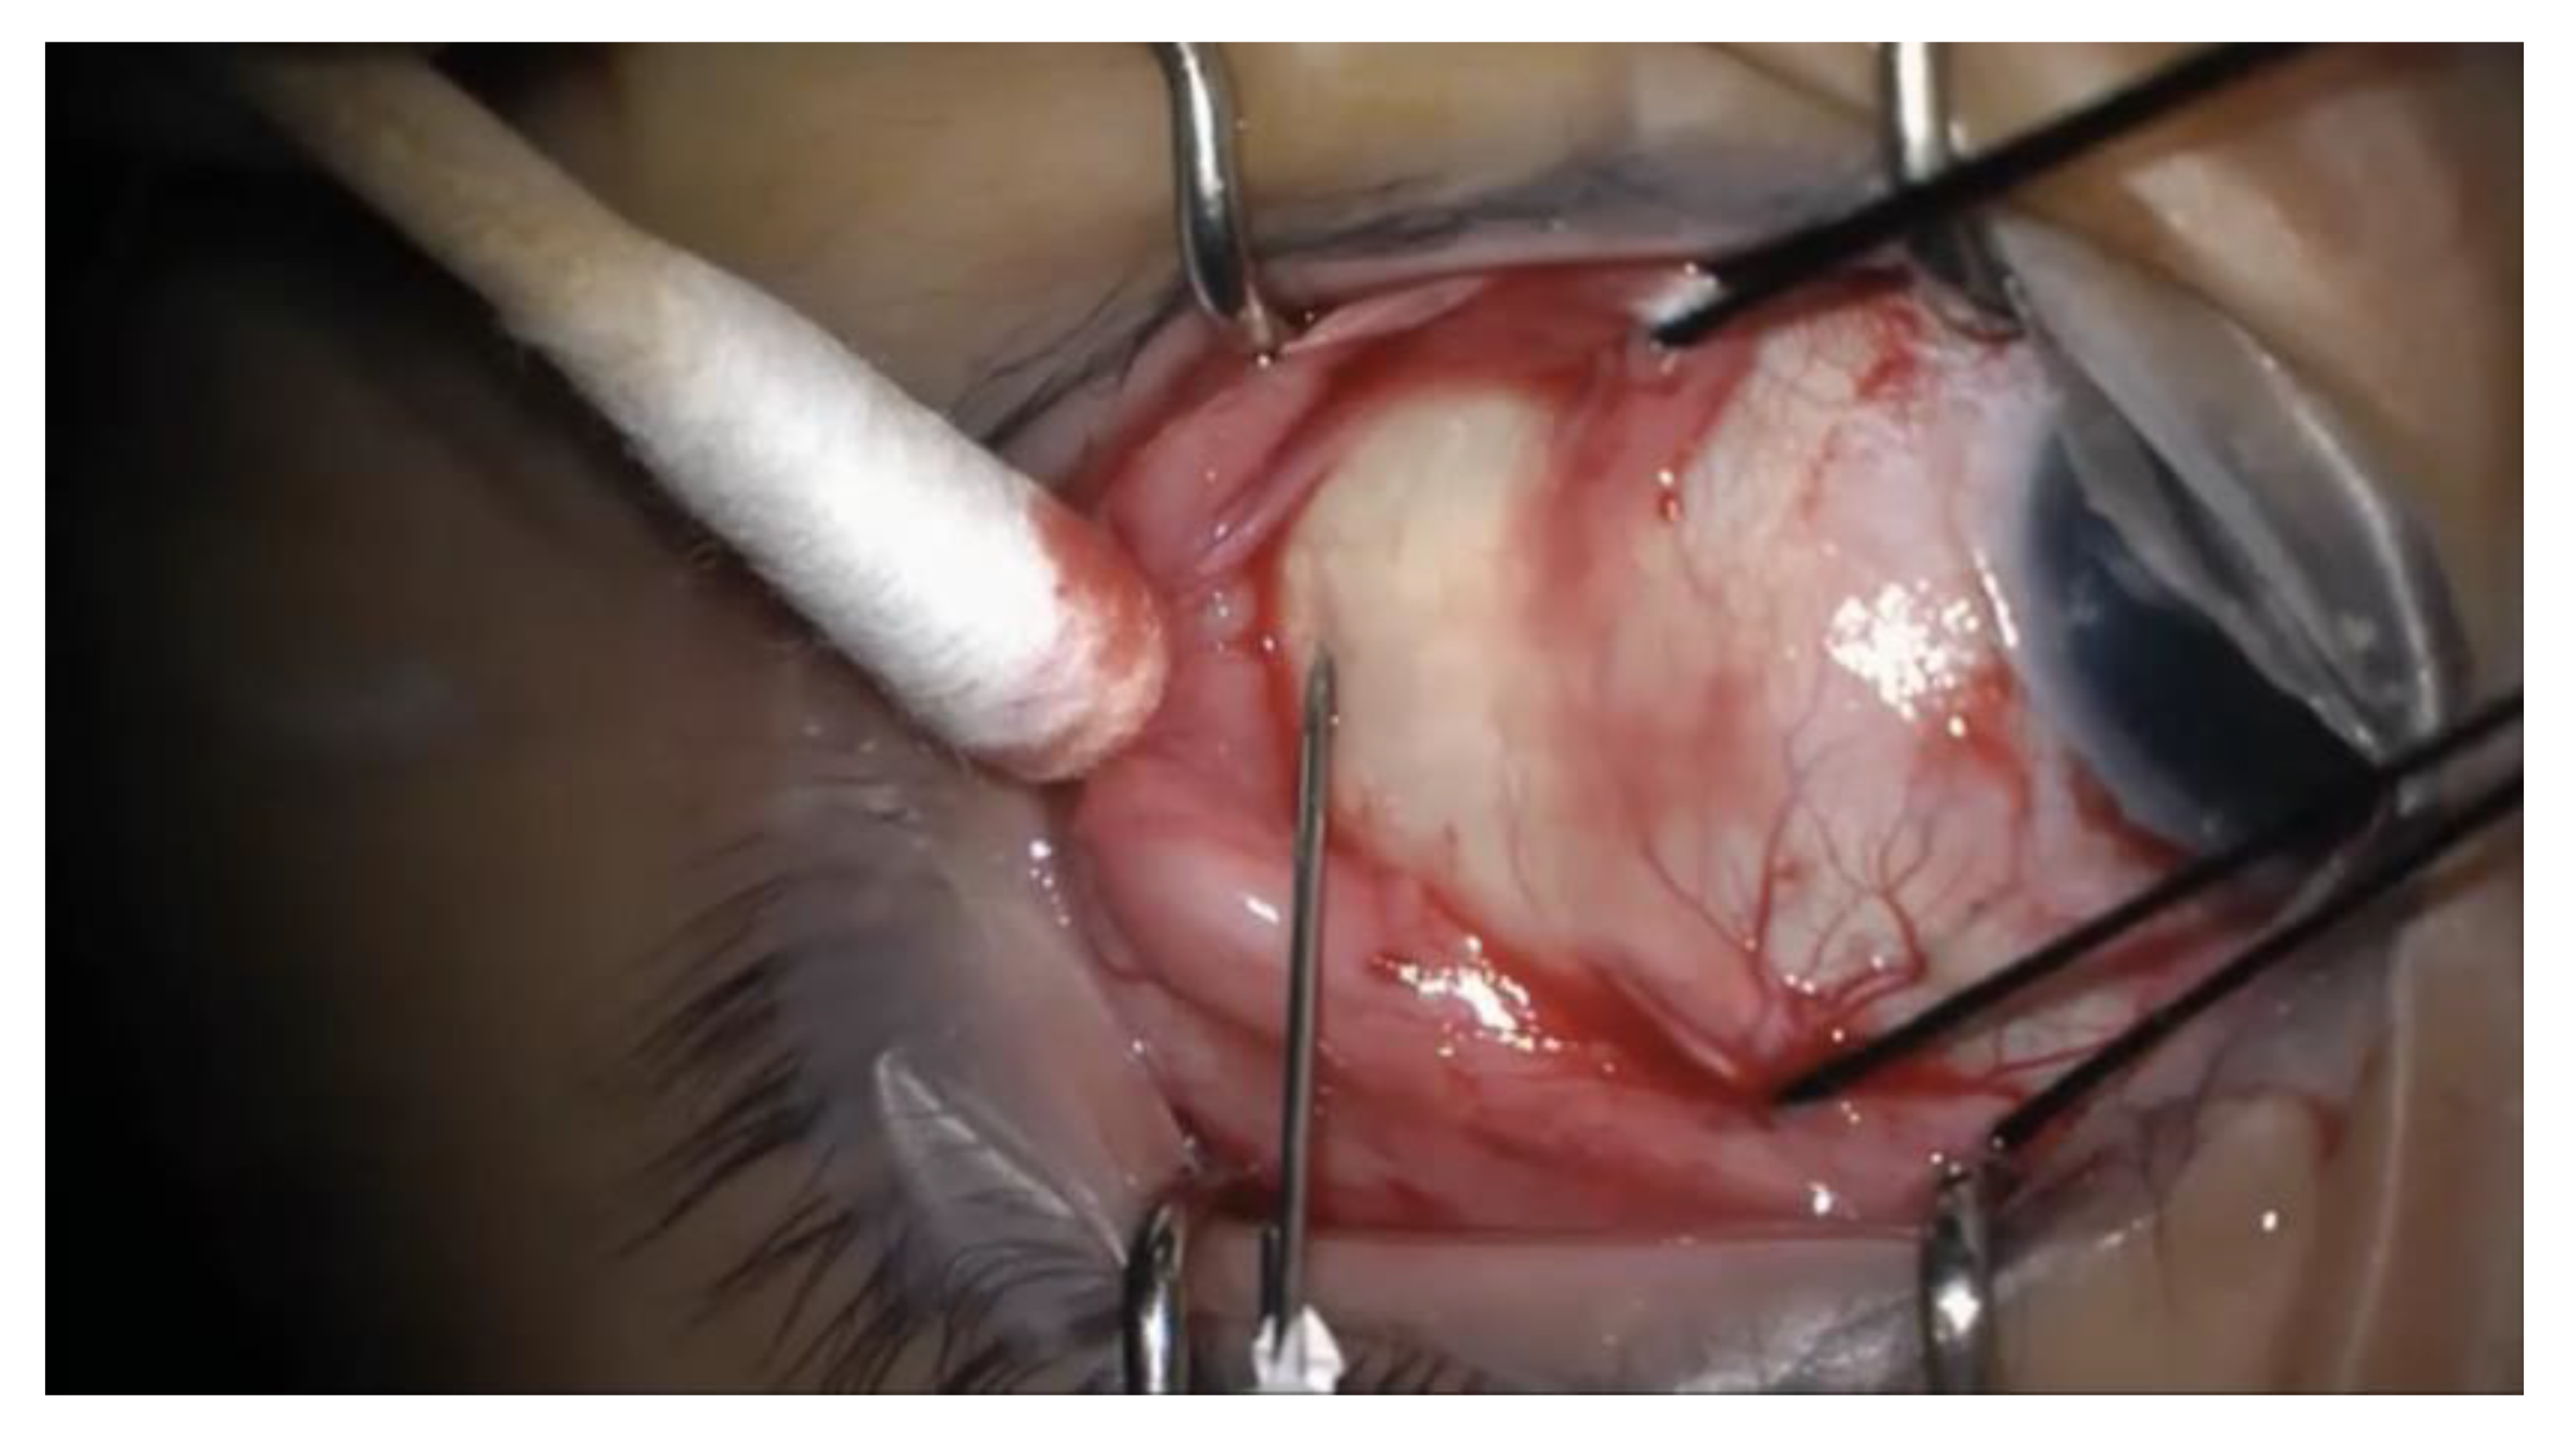

Westcott scissors were used to create a conjunctival peritomy in proportion to the anticipated circumference of the buckle, and the appropriate rectus muscle(s) were isolated. In conjunction with the noncontact viewing system of the operating microscope, a light pipe or chandelier via a trocar-cannula system was used to inspect the retina for areas of detachment and breaks. A 25-gauge needle on a tuberculin (TB) syringe was introduced at an oblique angle into the subretinal space, transclerally, in the area that was to be covered by the buckle. See Figure 1 for an intraoperative photograph of the needle insertion. The needle was removed immediately after entering the sclera. This stab incision was done without simultaneous visualization of the fundus. The SRF was expressed from the drainage site by depressing the posterior lip of the wound using a cotton swab. Careful inspection confirmed reattachment of the retina, and cryotherapy was applied in the location of the break(s). Nylon sutures (5-0), optionally placed before or after drainage of the subretinal fluid, were passed through the partial thickness of the sclera in a horizontal mattress fashion at 1 mm and 7 mm to 10 mm (depending on the buckle size) posterior to the level of the muscle insertion. The scleral buckle was subsequently passed beneath the sutures and the rectus muscle(s), with the two free ends joined with a sleeve for encircling buckles. For segmental buckles, the ends were left free with either one or two horizontal mattress sutures passed in each intermuscular quadrant containing retinal pathology. An anterior chamber paracentesis or injection of a sterile balanced salt solution (BSS) through the pars plana cannula was performed with a 30-gauge needle if needed to restore normal pressure. The buckle contour on the retina was visualized to ensure adequate support of the break, with adjustment via suture removal and replacement if necessary. Optic nerve perfusion was confirmed on ophthalmodynamometry. A representative surgical video demonstrates the surgical technique for one of the patients in this case series (accessible via the following link: https://tinyurl.com/5csb8php).

Figure 1.

Intraoperative photograph of the needle insertion for external drainage of subretinal fluid. A 25-gauge needle on a tuberculin syringe is introduced transclerally at an oblique angle into the subretinal space. The needle is removed immediately after entering the sclera, and subretinal fluid is expressed by depressing the posterior lip of the wound using a cotton swab.